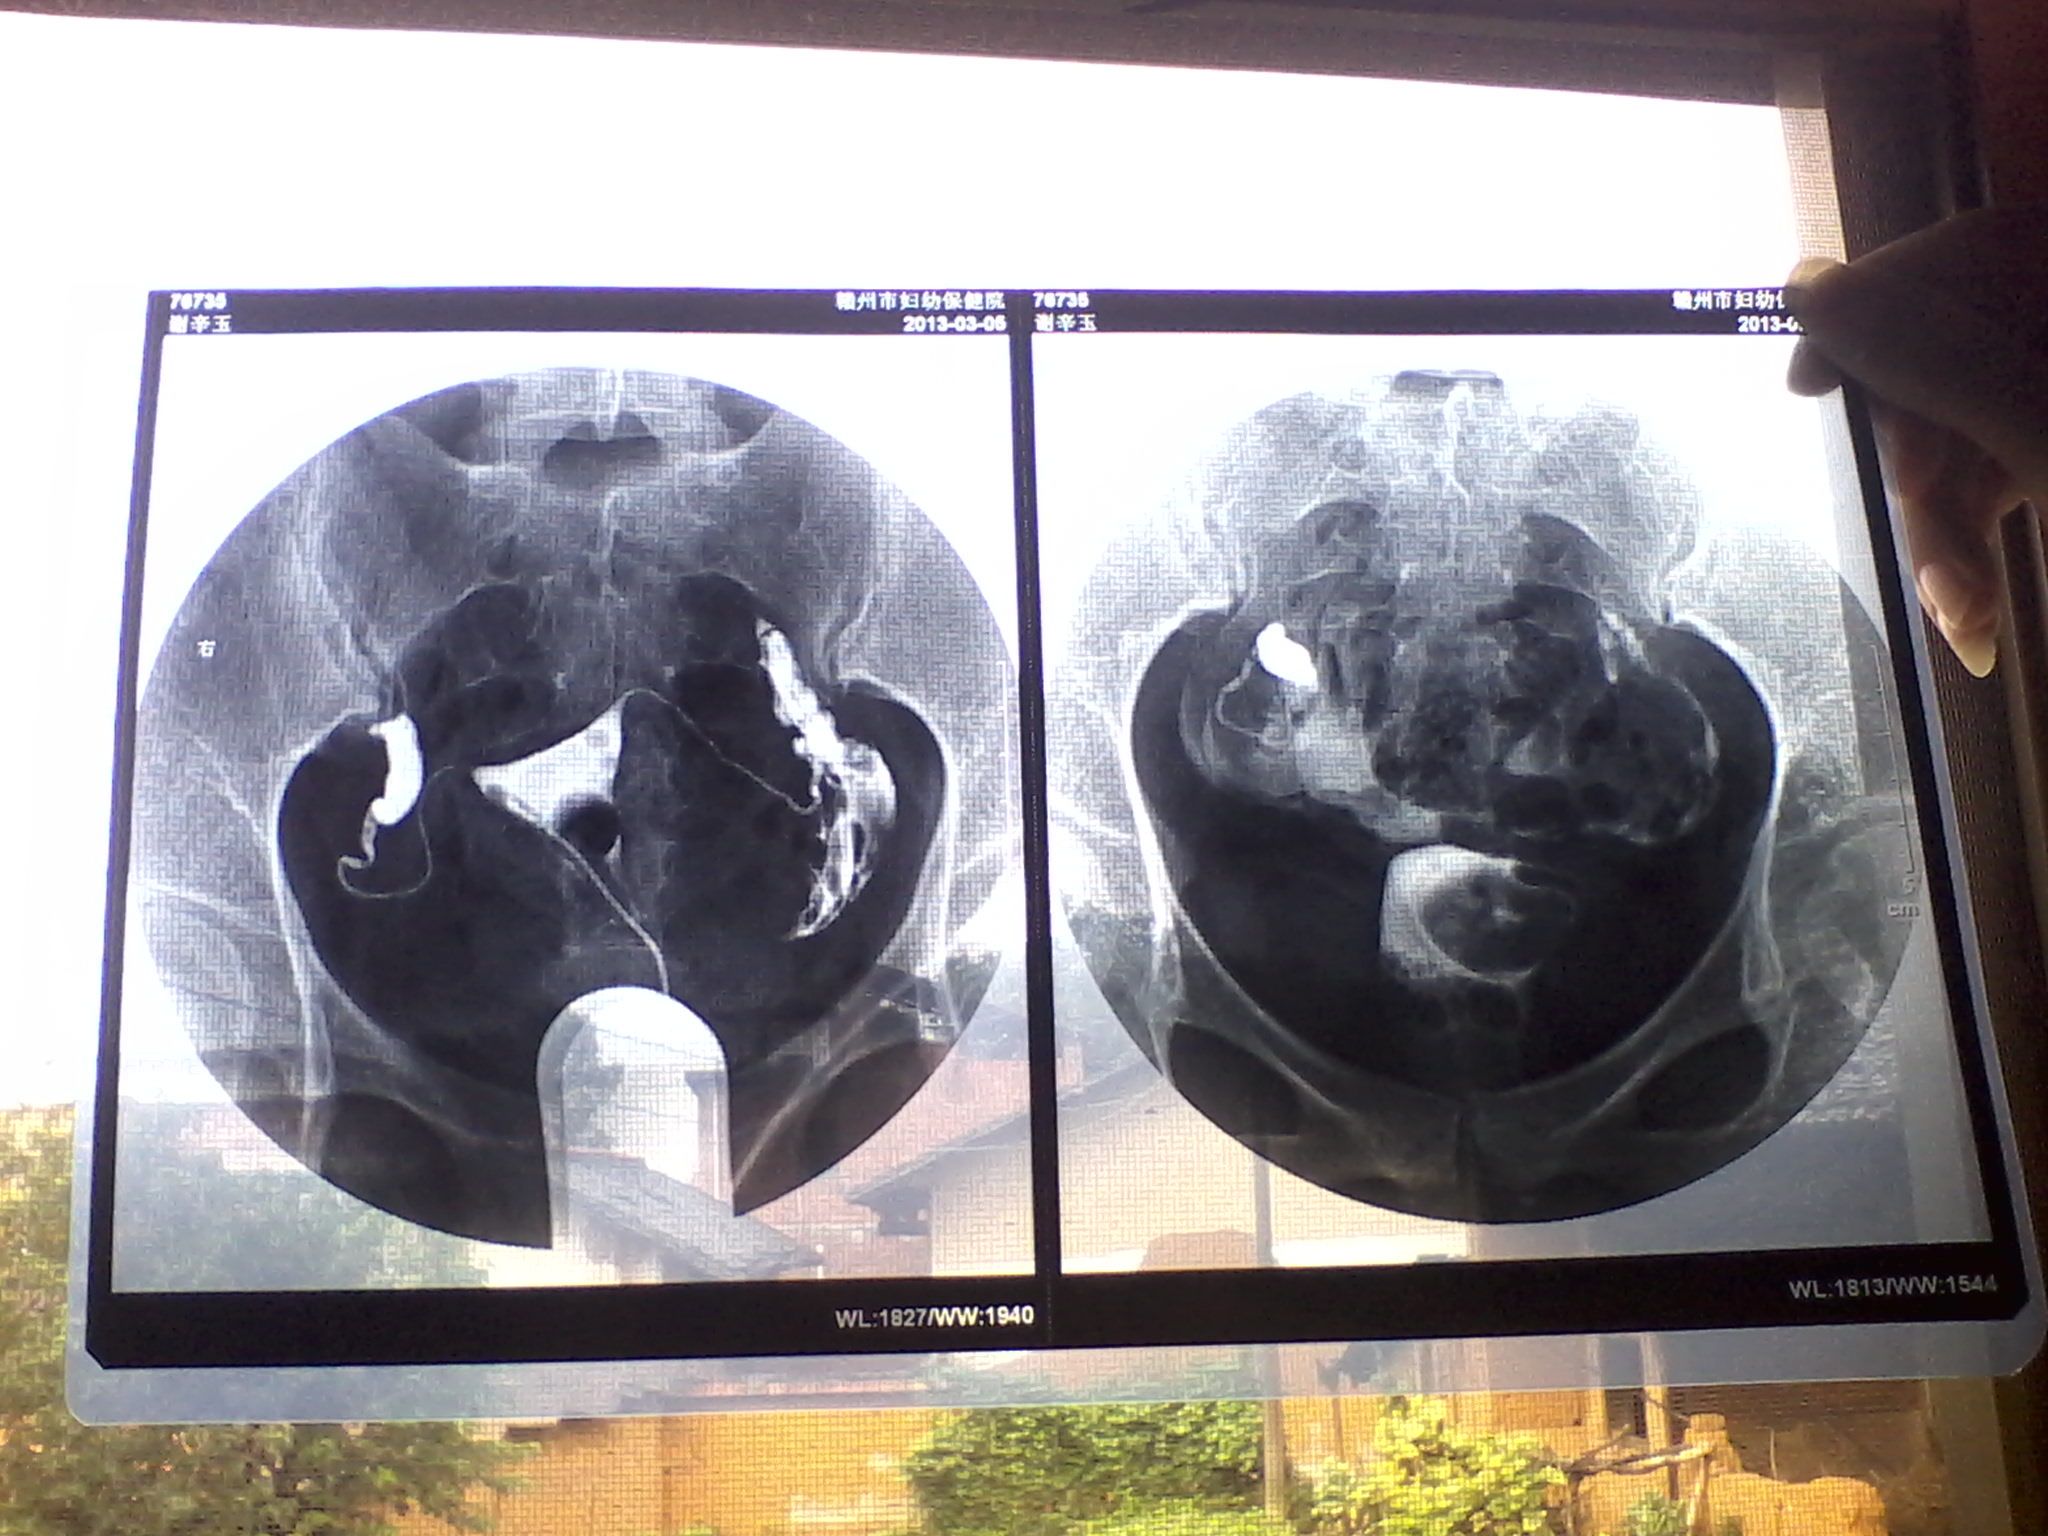

输卵管是存在于盆腔的一对肌性管概暖道,如寸做裕果一侧存在堵塞 多提示盆寸生腔内存在粘连带,这样的话就算是另一侧通畅 那么其正常的蠕动及拾卵功能也会受到限制 同样也会阻碍受孕

你现在的情况是左侧输卵管正常,那么你怀孕的机会只有百分之五十。你的右侧输卵管堵塞,那么建议尽早去检查,帮您对症进行治疗。治疗好了再开始备孕。